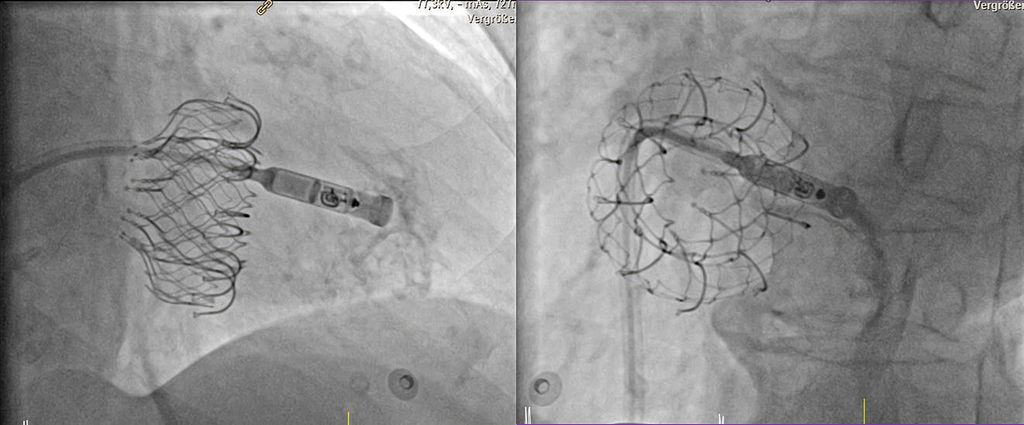

Abb. 4: Implantation eines sondenlosen Herzschrittmachers (Medtronic MicraTM) in den rechten Ventrikel bei vorbestehendem interventionellem Trikuspidalklappenersatz (EvoqueTM). Zur optimalen Positionierung wird über den Delivery-Katheter Kontrastmittel verabreicht. Die sondenlose Schrittmacherkapsel ist noch mit dem Delivery-Katheter verbunden. Links: Ansicht von schräg rechts vorne (RAO), rechts: Ansicht von schräg links vorne (LAO)